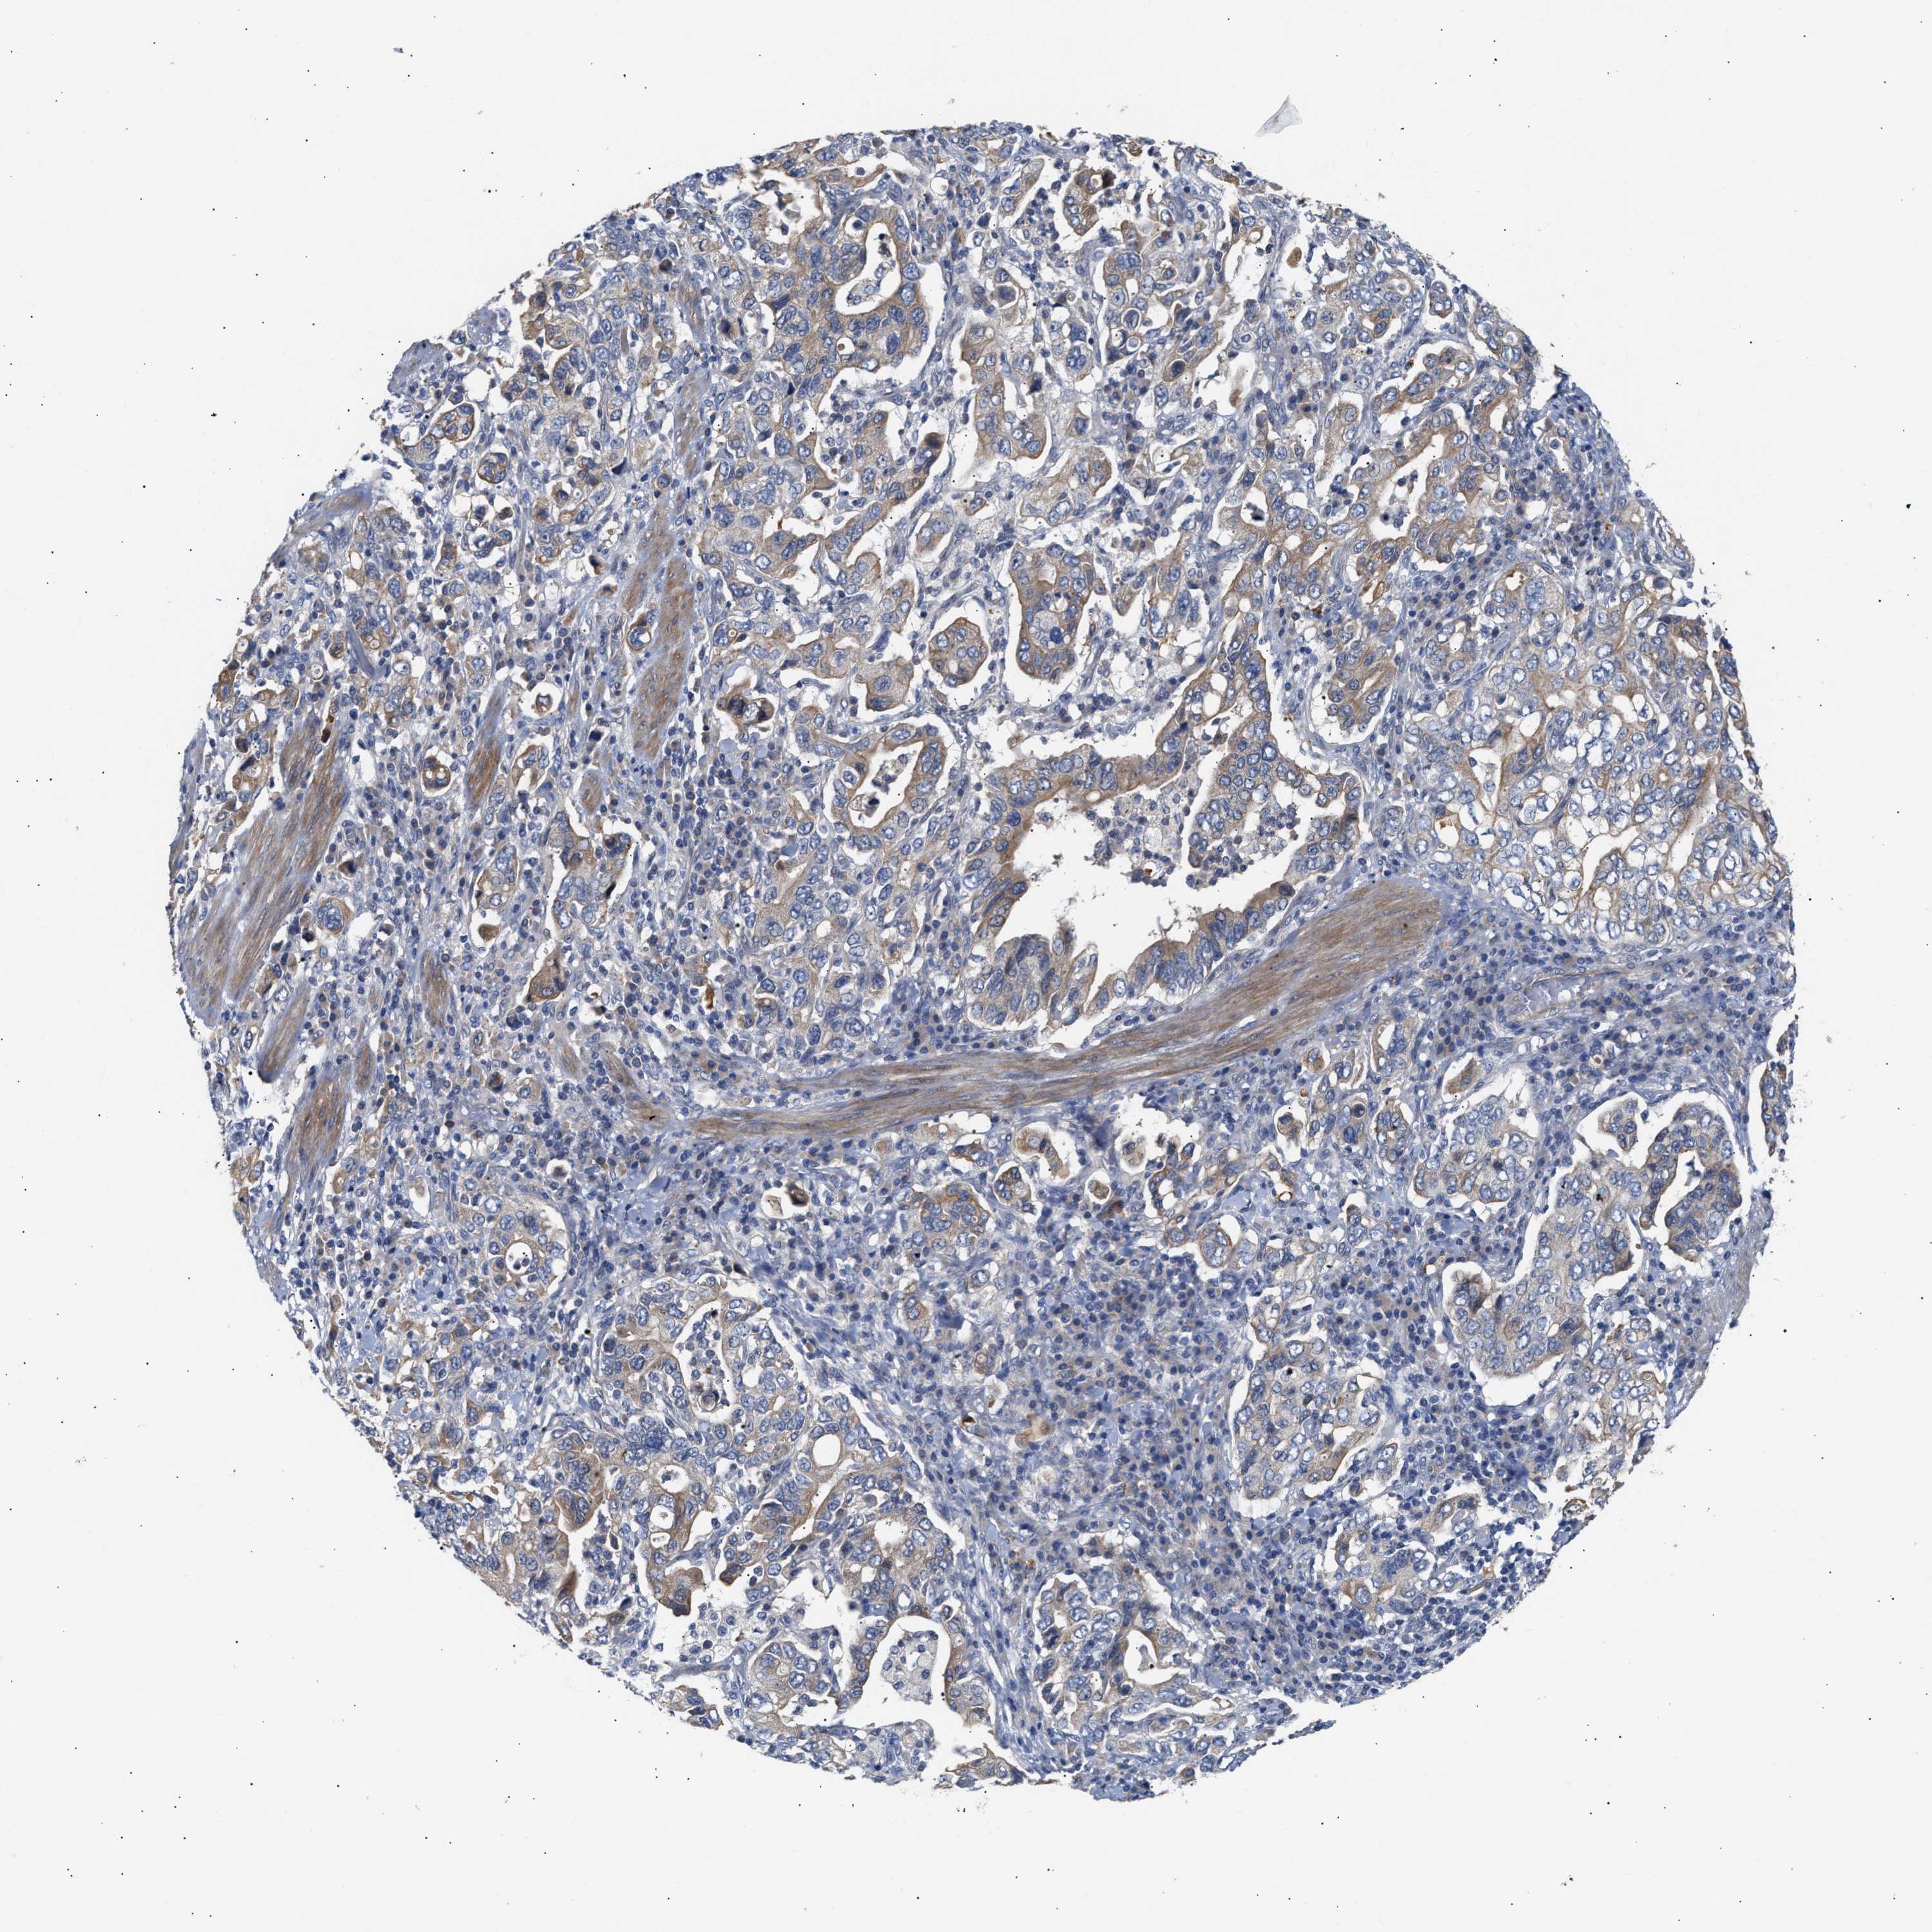

STOMACH CANCER - Protein expressioni

A mouse-over function shows sample information and annotation data. Click on an image to view it in a full screen mode. Samples can be filtered based on level of antibody staining by selecting one or several of the following categories: high, medium, low and not detected. The assay and annotation is described here.

Note that samples used for immunohistochemistry by the Human Protein Atlas do not correspond to samples in the TCGA dataset.

Antibody stainingi

Antibody staining in the annotated cell types in the current human tissue is reported as not detected, low, medium, or high, based on conventional immunohistochemistry profiling in selected tissues. This score is based on the combination of the staining intensity and fraction of stained cells.

Each image is clickable and will lead to virtual microscopy that enables deeper exploration of all samples and also displays staining intensity scores, fraction scores and subcellular localization as well as patient and tissue information for each sample.

Antibody HPA020082

Antibody HPA020105

Staining

High

Medium

Low

Not detected

Intensity

Strong

Moderate

Weak

Negative

Quantity

>75%

75%-25%

<25%

None

Location

Nuclear

Cytoplasmic/membranous

Cytoplasmic/membranous,nuclear

Adenocarcinoma, NOS